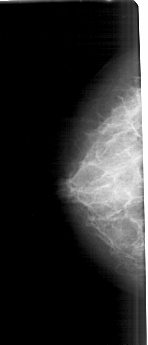

A_1682_1.LEFT_CC

LEFT_CC LINES 5161 PIXELS_PER_LINE 2206 BITS_PER_PIXEL 12 RESOLUTION 43.5 NON_OVERLAY